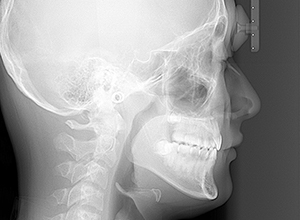

X-Ray

X-Ray所見

セファロ所見 下顎骨は比較的バランスが良いもののセラに対して下顎等は後方に位置しており中顔面部の奥行きもあることから顔面高さは低くなっていた。

パノラマ所見 上下顎第三大臼歯は埋伏歯しており、上顎右側犬歯は先天欠如をしていた。